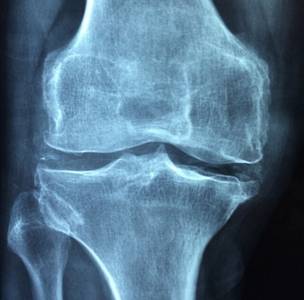

«Пиаскледин» используют для борьбы с остеоартрозом. Этот препарат имеет принципиально другой механизм действия, в отличие от традиционных медикаментов хондроитина и глюкозамина. Оригинальная формула содержит 6 действующих веществ и 24 фракции, в том числе фитостерины, фосфолипиды и др. Компоненты подобраны в оптимальном соотношении, что обеспечивает эффективность препарата. Подробнее о «Пиаскледине», цене на него, как он работает и для чего нужен, мы поговорим ниже.

Препарат назначают в комплексной терапии остеоартроза тазобедренных и коленных суставов I-III стадии, для адъювантной терапии периодонтитов.